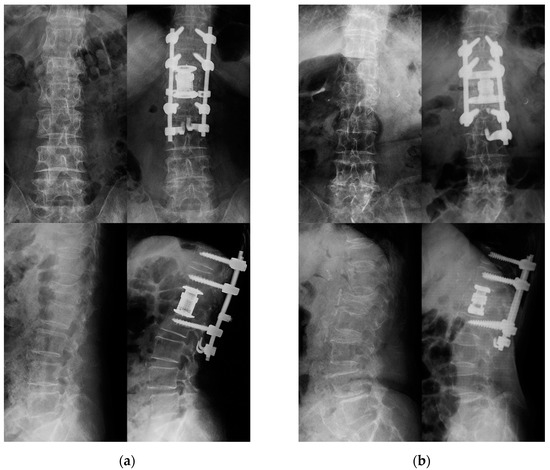

- Nakashima, H.; Kanemura, T.; Satake, K.; Ito, K.; Tanaka, S.; Segi, N.; Ouchida, J.; Ando, K.; Kobayashi, K.; Ishiguro, N.; et al. Lateral Approach Corpectomy and Reconstruction after Anterior Longitudinal Ligament Release in Cases with Fixed Kyphosis: A Technical Note and a Preliminary Case Series. J. Clin. Neurosci. 2020, 78, 164–169. [Google Scholar] [CrossRef] [PubMed]